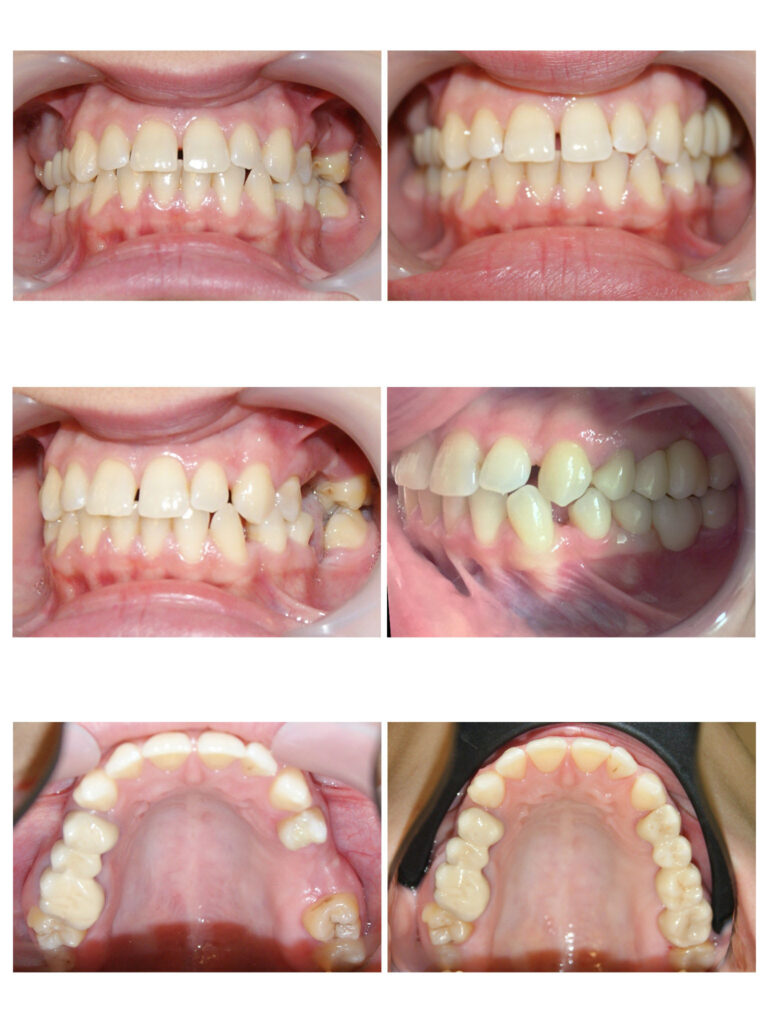

Caz cu extracție de 2 premolari pentru alinierea caninilor